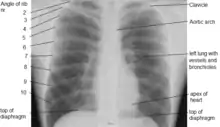

Thorax

The thorax (PL: thoraces or thoraxes)[1] or chest is a part of the anatomy of humans, mammals, and other tetrapod animals located between the neck and the abdomen.[2][3] In insects, crustaceans, and the extinct trilobites, the thorax is one of the three main divisions of the creature's body, each of which is in turn composed of multiple segments.

The human thorax includes the thoracic cavity and the thoracic wall. It contains organs including the heart, lungs, and thymus gland, as well as muscles and various other internal structures. Many diseases may affect the chest, and one of the most common symptoms is chest pain.

In humans and other hominids, the thorax is the chest region of the body between the neck and the abdomen, along with its internal organs and other contents. It is mostly protected and supported by the rib cage, spine, and shoulder girdle.

The contents of the thorax include the heart and lungs (and the thymus gland); the major and minor pectoral muscles, trapezius muscles, and neck muscle; and internal structures such as the diaphragm, the esophagus, the trachea, and a part of the sternum known as the xiphoid process. Arteries and veins are also contained – (aorta, superior vena cava, inferior vena cava and the pulmonary artery); bones (the shoulder socket containing the upper part of the humerus, the scapula, sternum, thoracic portion of the spine, collarbone, and the rib cage and floating ribs).